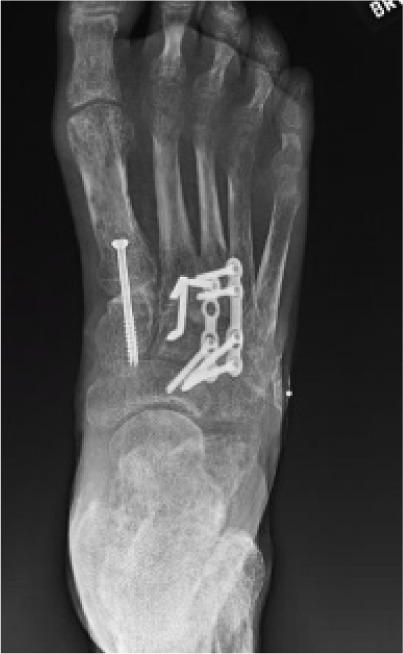

Following clinical resolution of infection, the second stage involved definitive deformity correction. A Lapidus bunionectomy with fusion of the first tarsometatarsal joint was performed to correct medial column instability and hallux valgus deformity. Concurrently, hammertoe corrections of the second through fifth digits were completed using arthrodesis techniques to address rigid digital contractures contributing to abnormal lateral forefoot pressure (Figure 11).

FIGURE 11 Postoperative image at 12 weeks showing healed lateral forefoot with corrected alignment.

In the third and final stage, elective removal of hardware was performed after radiographic evidence confirmed successful fusion and alignment (Figure 12). This was done to reduce long-term risk of hardware prominence or skin breakdown, particularly given the patient’s history of ulceration and peripheral neuropathy.

FIGURE 12 Radiograph confirming Lapidus fusion consolidation and digital realignment.